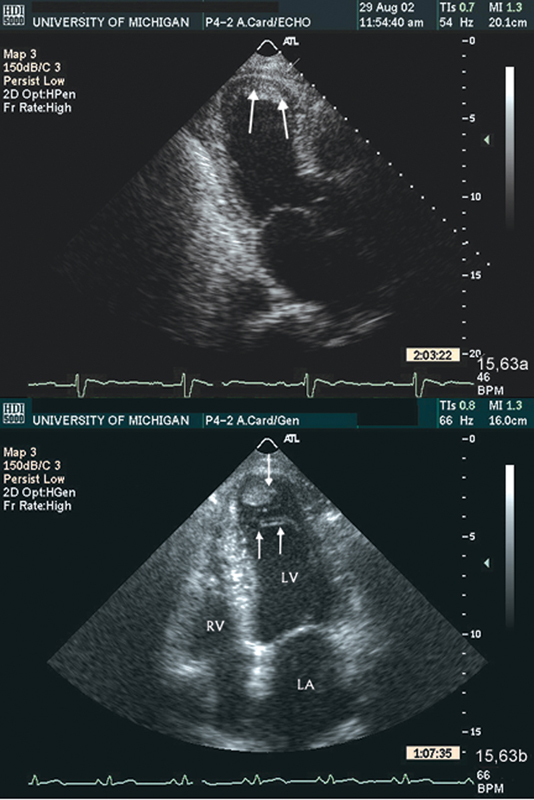

فحوصات تشخيصية لبعض امراض القلب والشرايين التاجية